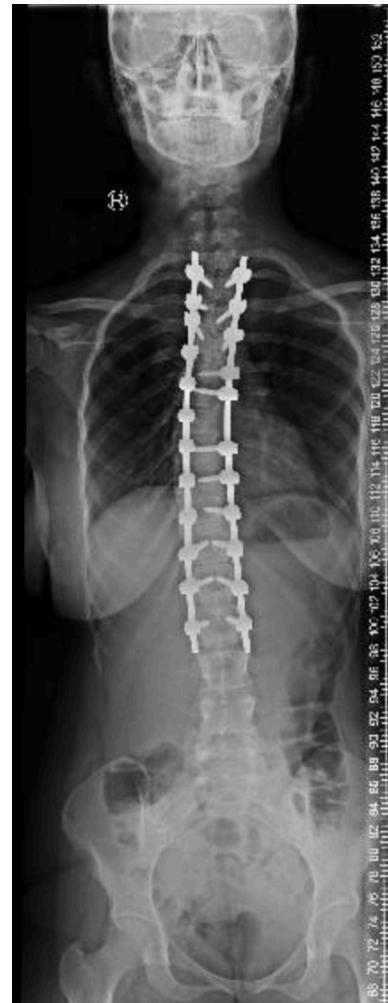

Scoliosis

Deformities

Scoliosis Classification

- Adolescent Idiopathic Scoliosis

- Infantile Idiopathic Scoliosis

- Congenital Scoliosis

- Neuromuscular Scoliosis: Irregular spinal curvature caused by disorders of brain, spinal cord, and muscular system

Adolescent Idiopathic Scoliosis

- Definition: Coronal plane spinal deformity most commonly presenting in adolescent girls from ages 10 to 18

Imaging:

Severity Grades:

- Mild: 10-25°

- Moderate: 25-45°

- Severe: >45°

Treatment Based on Severity:

- Observation: Mild curves, depending on age and skeletal maturity

- Bracing: Moderate curves (25-45°) in growing patients

- Surgery: Severe curves (>45°) or progressive curves